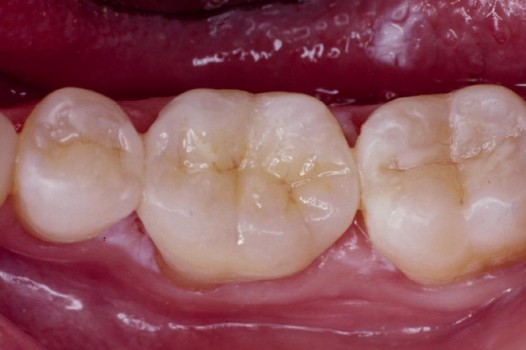

Traditional amalgam (mercury) fillings have been used for over a century, but concerns about health risks, tooth fractures, and long-term decay have led many dentists to adopt modern alternatives. Today, metal-free restorations offer healthier, stronger, and more natural-looking results.

Using advanced resins, ceramics, and state-of-the-art bonding techniques, Dr. Klim can restore teeth with precision, preserving healthy tooth structure while preventing fractures, bacterial invasion, and future toothaches.